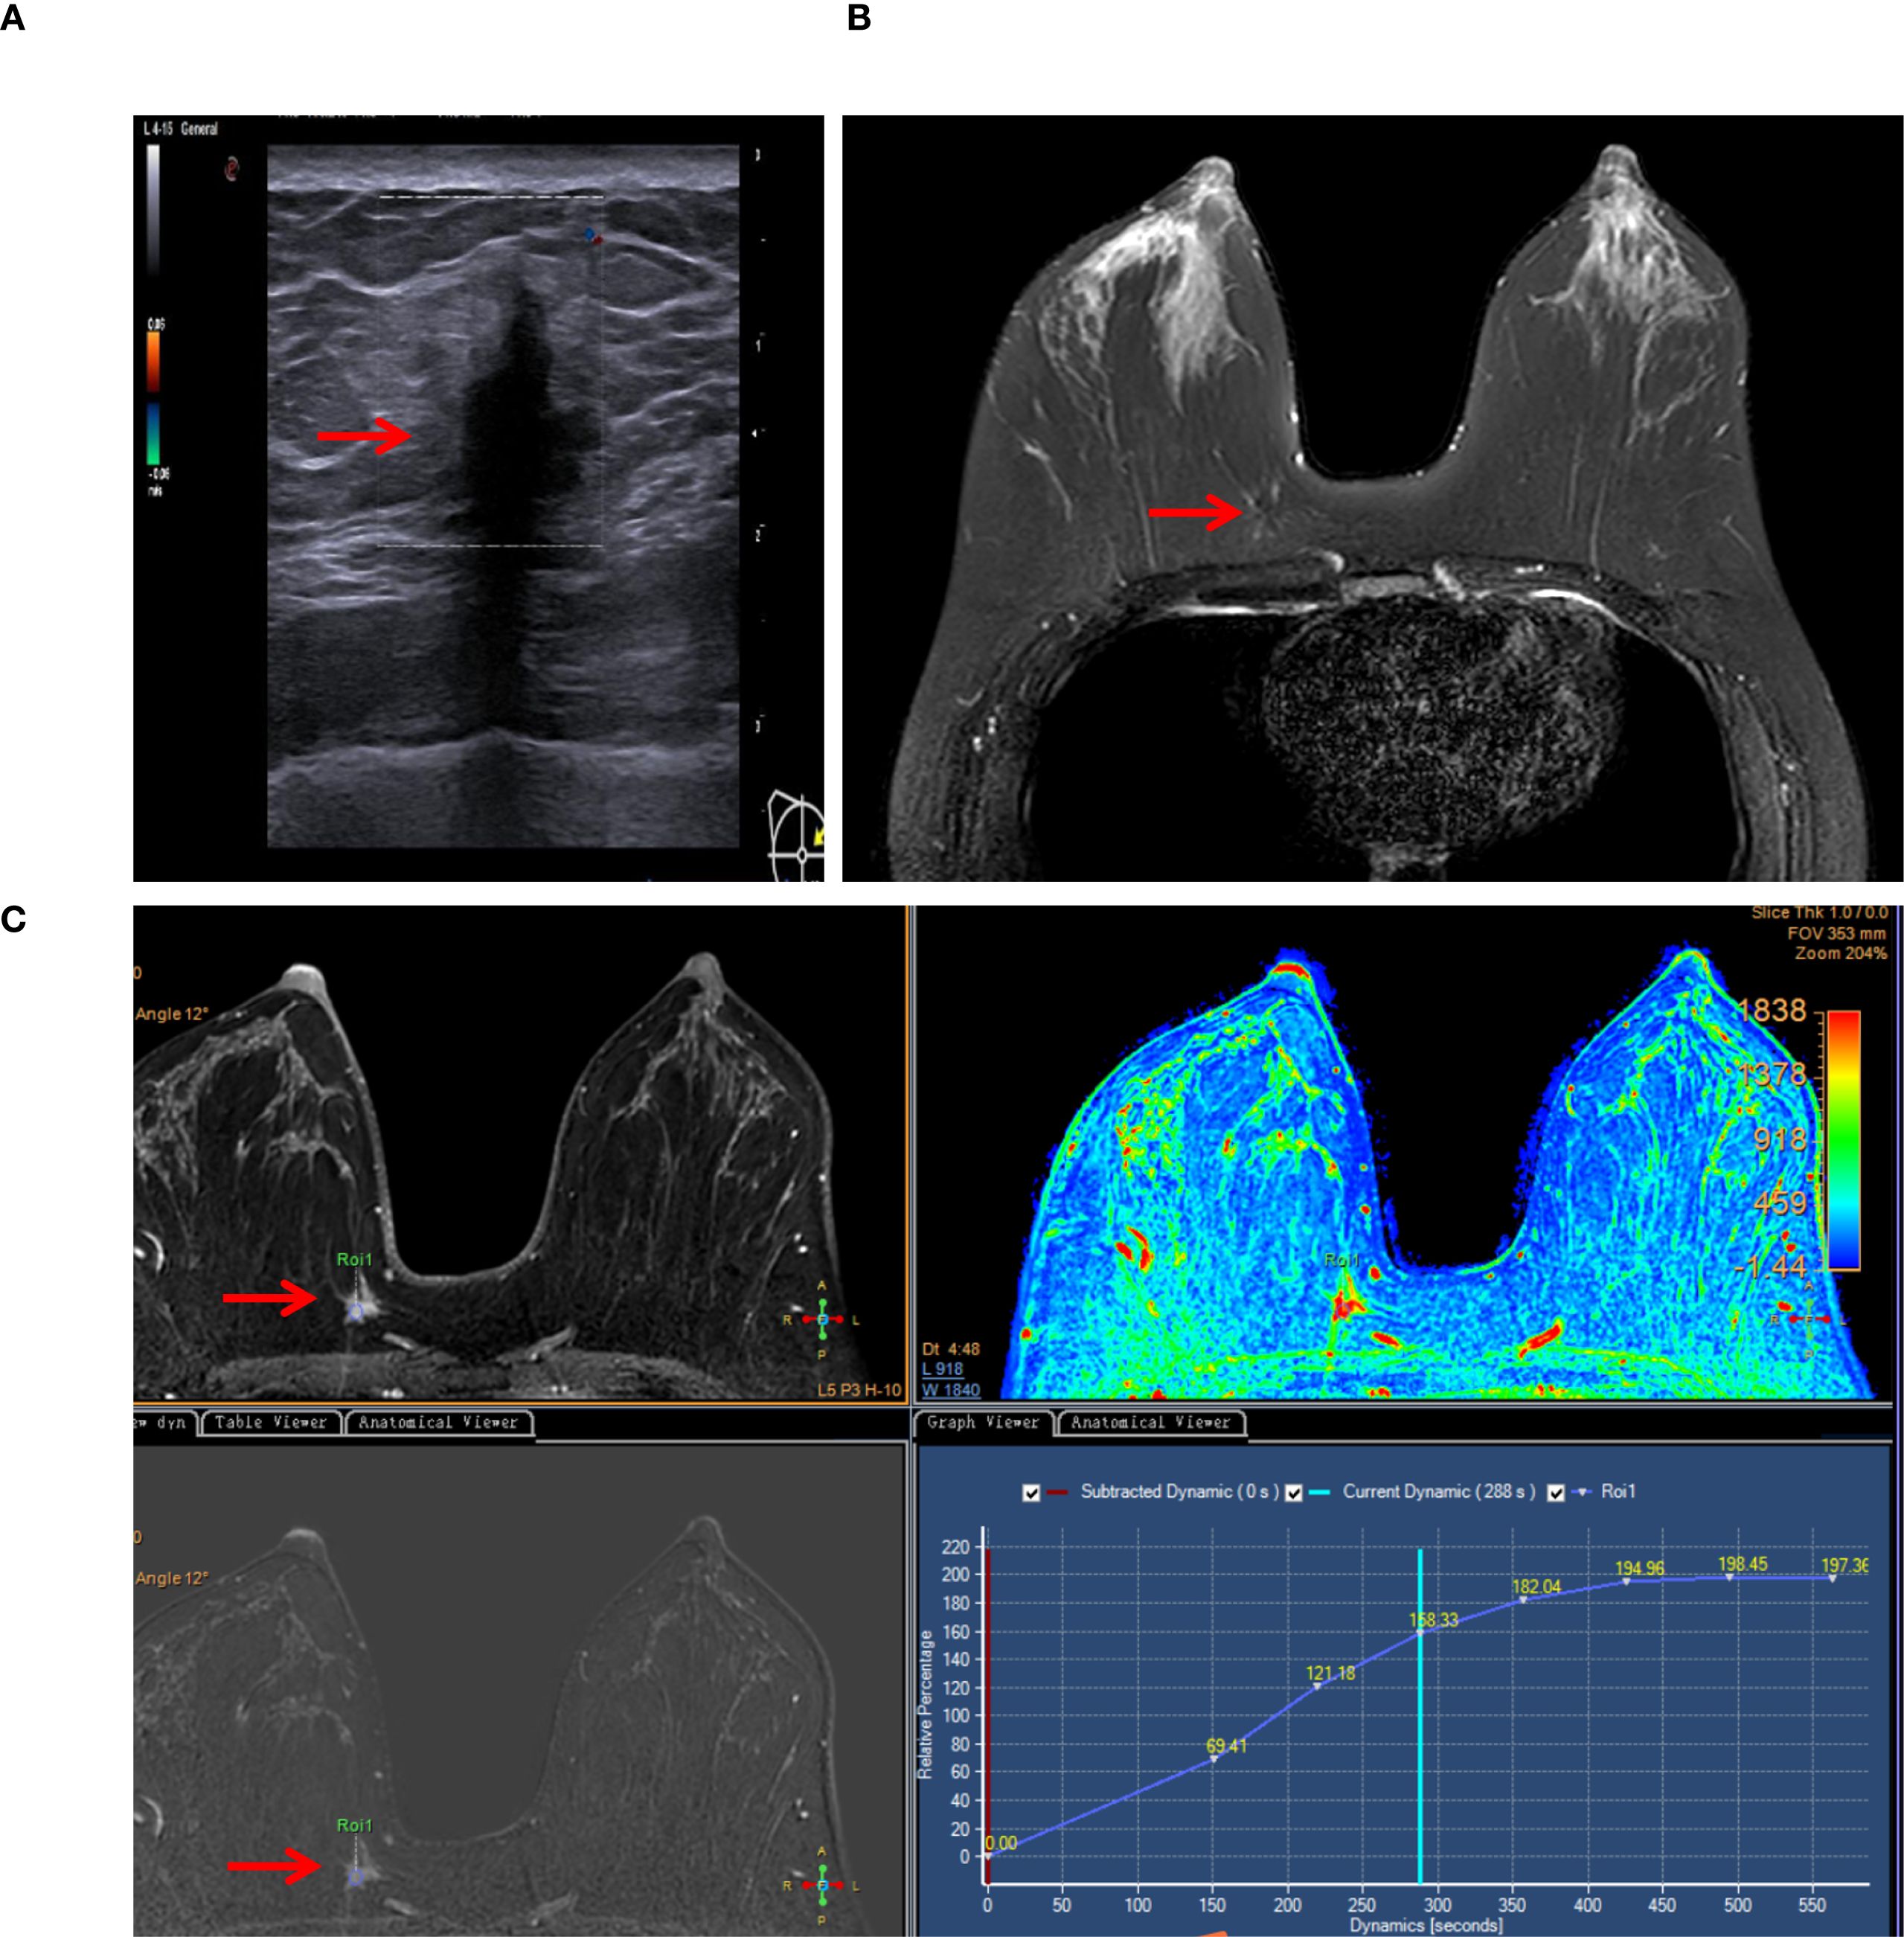

A 39-year-old woman presented to our department with a 10-day history of a right breast mass, initially detected during a routine health check-up. She had no known personal or family history of breast cancer. Physical examination revealed a palpable and firm and painless mass in the upper inner quadrant of the right breast, with unclear margins. No enlarged lymph nodes were palpable in the right axilla. Color Doppler ultrasonography of the right breast identified a hypoechoic nodule at the 2–3:00 position at the edge of the glandular tissue in the right breast (Figure 1A). The nodule measured approximately 15 mm × 15 mm × 14 mm, with an irregular shape, angulated and spiculated margins, uniform internal echoes, significant posterior acoustic shadowing, and no obvious blood flow signal. It was classified as the Breast Imaging Reporting and Data System (BI-RADS) Category 4B. Breast MRI showed a mass in the upper inner quadrant of the right breast, measuring approximately 15 mm × 13 mm × 8 mm. The mass exhibited low signal intensity on T1-weighted imaging (T1WI), slightly high signal intensity on T2-weighted imaging (T2WI) (Figure 1B), central low signal intensity, and slightly high signal intensity on diffusion-weighted imaging (DWI). Apparent diffusion coefficient (ADC) mapping revealed reduced signal intensity, and dynamic contrast enhancement demonstrated homogeneous enhancement. The time-intensity curve (TIC) exhibited a slow-rising pattern, and the lesion was classified as BI-RADS 4B (Figure 1C). Mammography was not performed due to the lesion’s small size, its location in the upper-inner quadrant of the right breast edge, and its proximity to the chest wall, which rendered mammography unsuitable for evaluation. Computed tomography (CT) of chest and abdominal ultrasonography showed no abnormalities. There was no evidence of axillary lymph node enlargement according to her imaging findings.

Figure 1. Typical imaging findings (lesion marked by arrows). (A) Color Doppler ultrasonography detected a noncapsular mass in the upper inner quadrant of the right breast (15×15×14 mm). (B) Breast MRI revealed a mass in the right breast (15×13×8 mm), exhibiting slightly high signal intensity on T2-weighted imaging (T2WI). (C) MRI dynamic contrast enhancement, silhouette image, Apparent diffusion coefficient (ADC) mapping (pseudo-color image), dynamic contrast enhancement and the time-intensity curve (TIC).